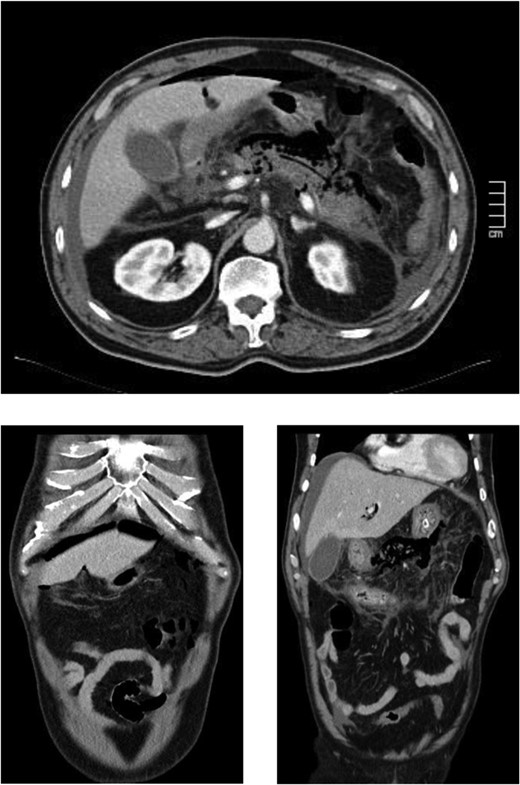

The case report refers to a 62-year-old man with medical history of hypertension, dyslipidemia and previous coronary stent placement. He went to the emergency department with upper abdominal pain with few hours of onset and vomits. The initial serum amylase was 2306 U/L and urinary amylase was 14 231 U/L. He met only one Ranson criteria at admission (Table 1). The first CT showed signs of a non-complicated acute pancreatitis (Fig. 1). He remained under surveillance and suffered clinical deterioration with progressive abdominal pain and tenderness and for this reason he was admitted on the intensive care unit (with an APACHE II score at admission of 15) where he progressed rapidly to multiple organ failure in <24 h. Due to this sudden worsening, with suspicion of a bowel perforation, a new CT scan was performed, showing significant gas dissection through the fascial planes with pneumoperitoneum and pneumoretroperitoneum (Fig. 2), however, without extraluminal contrast leakage evidence. This radiological gaseous pattern could not exclude a visceral perforation and raised the possibility of an anaerobe gas-producing bacteria presence. This sudden and progressive clinical deterioration together with an uncertain perforation or even an infected pancreatitis requiring for drainage motivated the beginning of empiric antibiotherapy with Meropenem and Metronidazol and an exploratory laparotomy on the operating room.

(After 16 h) Signs of necrotizing pancreatitis with pneumoperitoneum and pneumoretroperitoneum, pneumobilia and air on the main pancreatic duct.